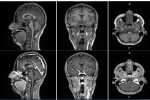

MRI contrast agents enhance the visualization of abnormal structures or lesions during imaging procedures and help clinicians better distinguish between healthy and diseased tissue. Mangaciclanol is intended for general-purpose MR imaging and demonstrates comparable relaxivity (the ability to enhance signal intensity) to market-leading gadolinium-based agent, gadobutrol, with early clinical images suggesting similar diagnostic capability. Unlike gadolinium, which is a rare-earth metal, manganese is present in our food, and is an endogenous element, naturally occurring and autoregulated in the body. The macrocyclic ‘cage-like’ structure of mangaciclanol lessens the possibility of retention.